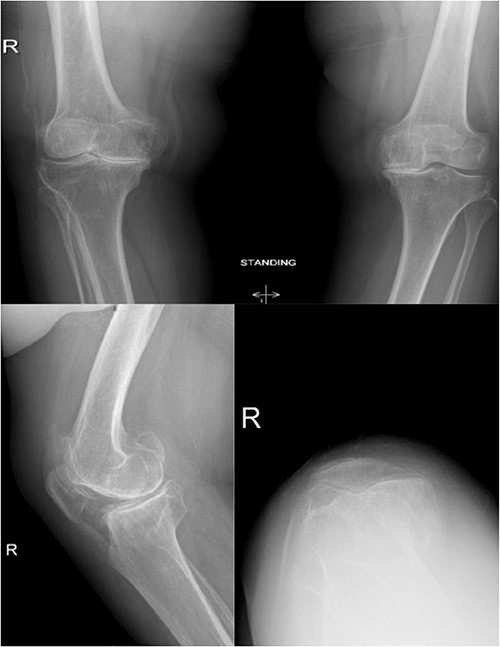

A 66-year-old woman with a history of right femoral shaft fracture, which was managed conservatively and resulted in malunion with right varus knee deformity. At the age of 54 years, she was diagnosed with osteoarthritis, and conservative treatment options, including weight reduction, non-steroidal anti-inflammatory medications, physiotherapy and intra-articular steroid injections, had been exhausted. Knee pain continued to worsen over the years, with negligible improvement in her symptoms. On physical examination, there was obvious varus deformity of the right knee, and significant restriction in the range of motion from full extension to 90° flexion. X-rays were requested, which revealed severe tri-compartmental knee osteoarthritis, a 3 cm medial shift of the right lower-limb mechanical axis, and 80° anatomical lateral distal femoral angle (aLDFA) and 96° mechanical lateral distal femoral angle (mLDFA) (Figs 1 and 2). The findings were discussed with the patient, who agreed to proceed with TKA. Given the complexity of this case with the femur deformity, the CORI Smith & Nephew surgical arthroplasty system was recommended as the surgical option that was suited to the patient’s specific bony anatomy and appropriate positioning of the components.

Preoperative anteroposterior, lateral and sunrise radiograph views displaying tri-compartmental osteoarthritis.